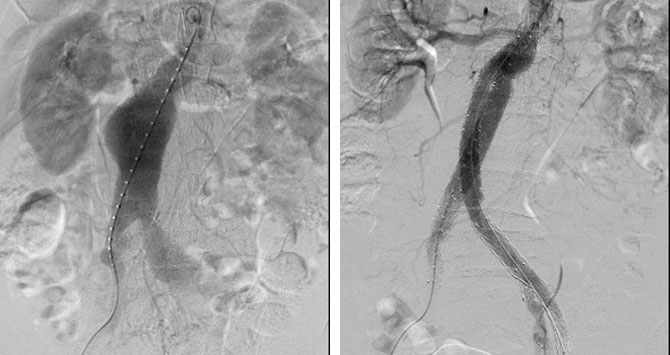

左图:术中造影可见腹主动脉、左侧髂总动脉瘤样扩张凸起;

右图:术后造影显示瘤体被很好隔绝,血管不再扩张凸起,左侧髂内动脉血流也通畅